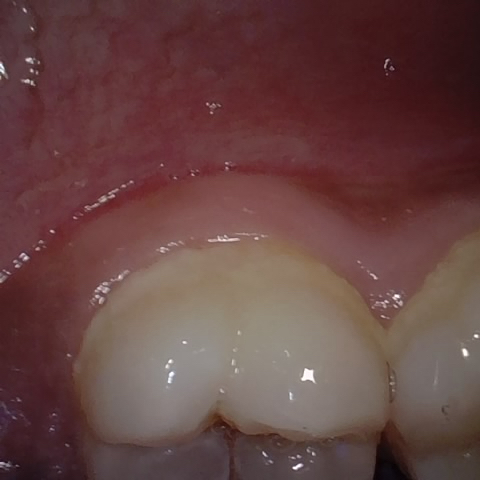

Annotated as "Good"